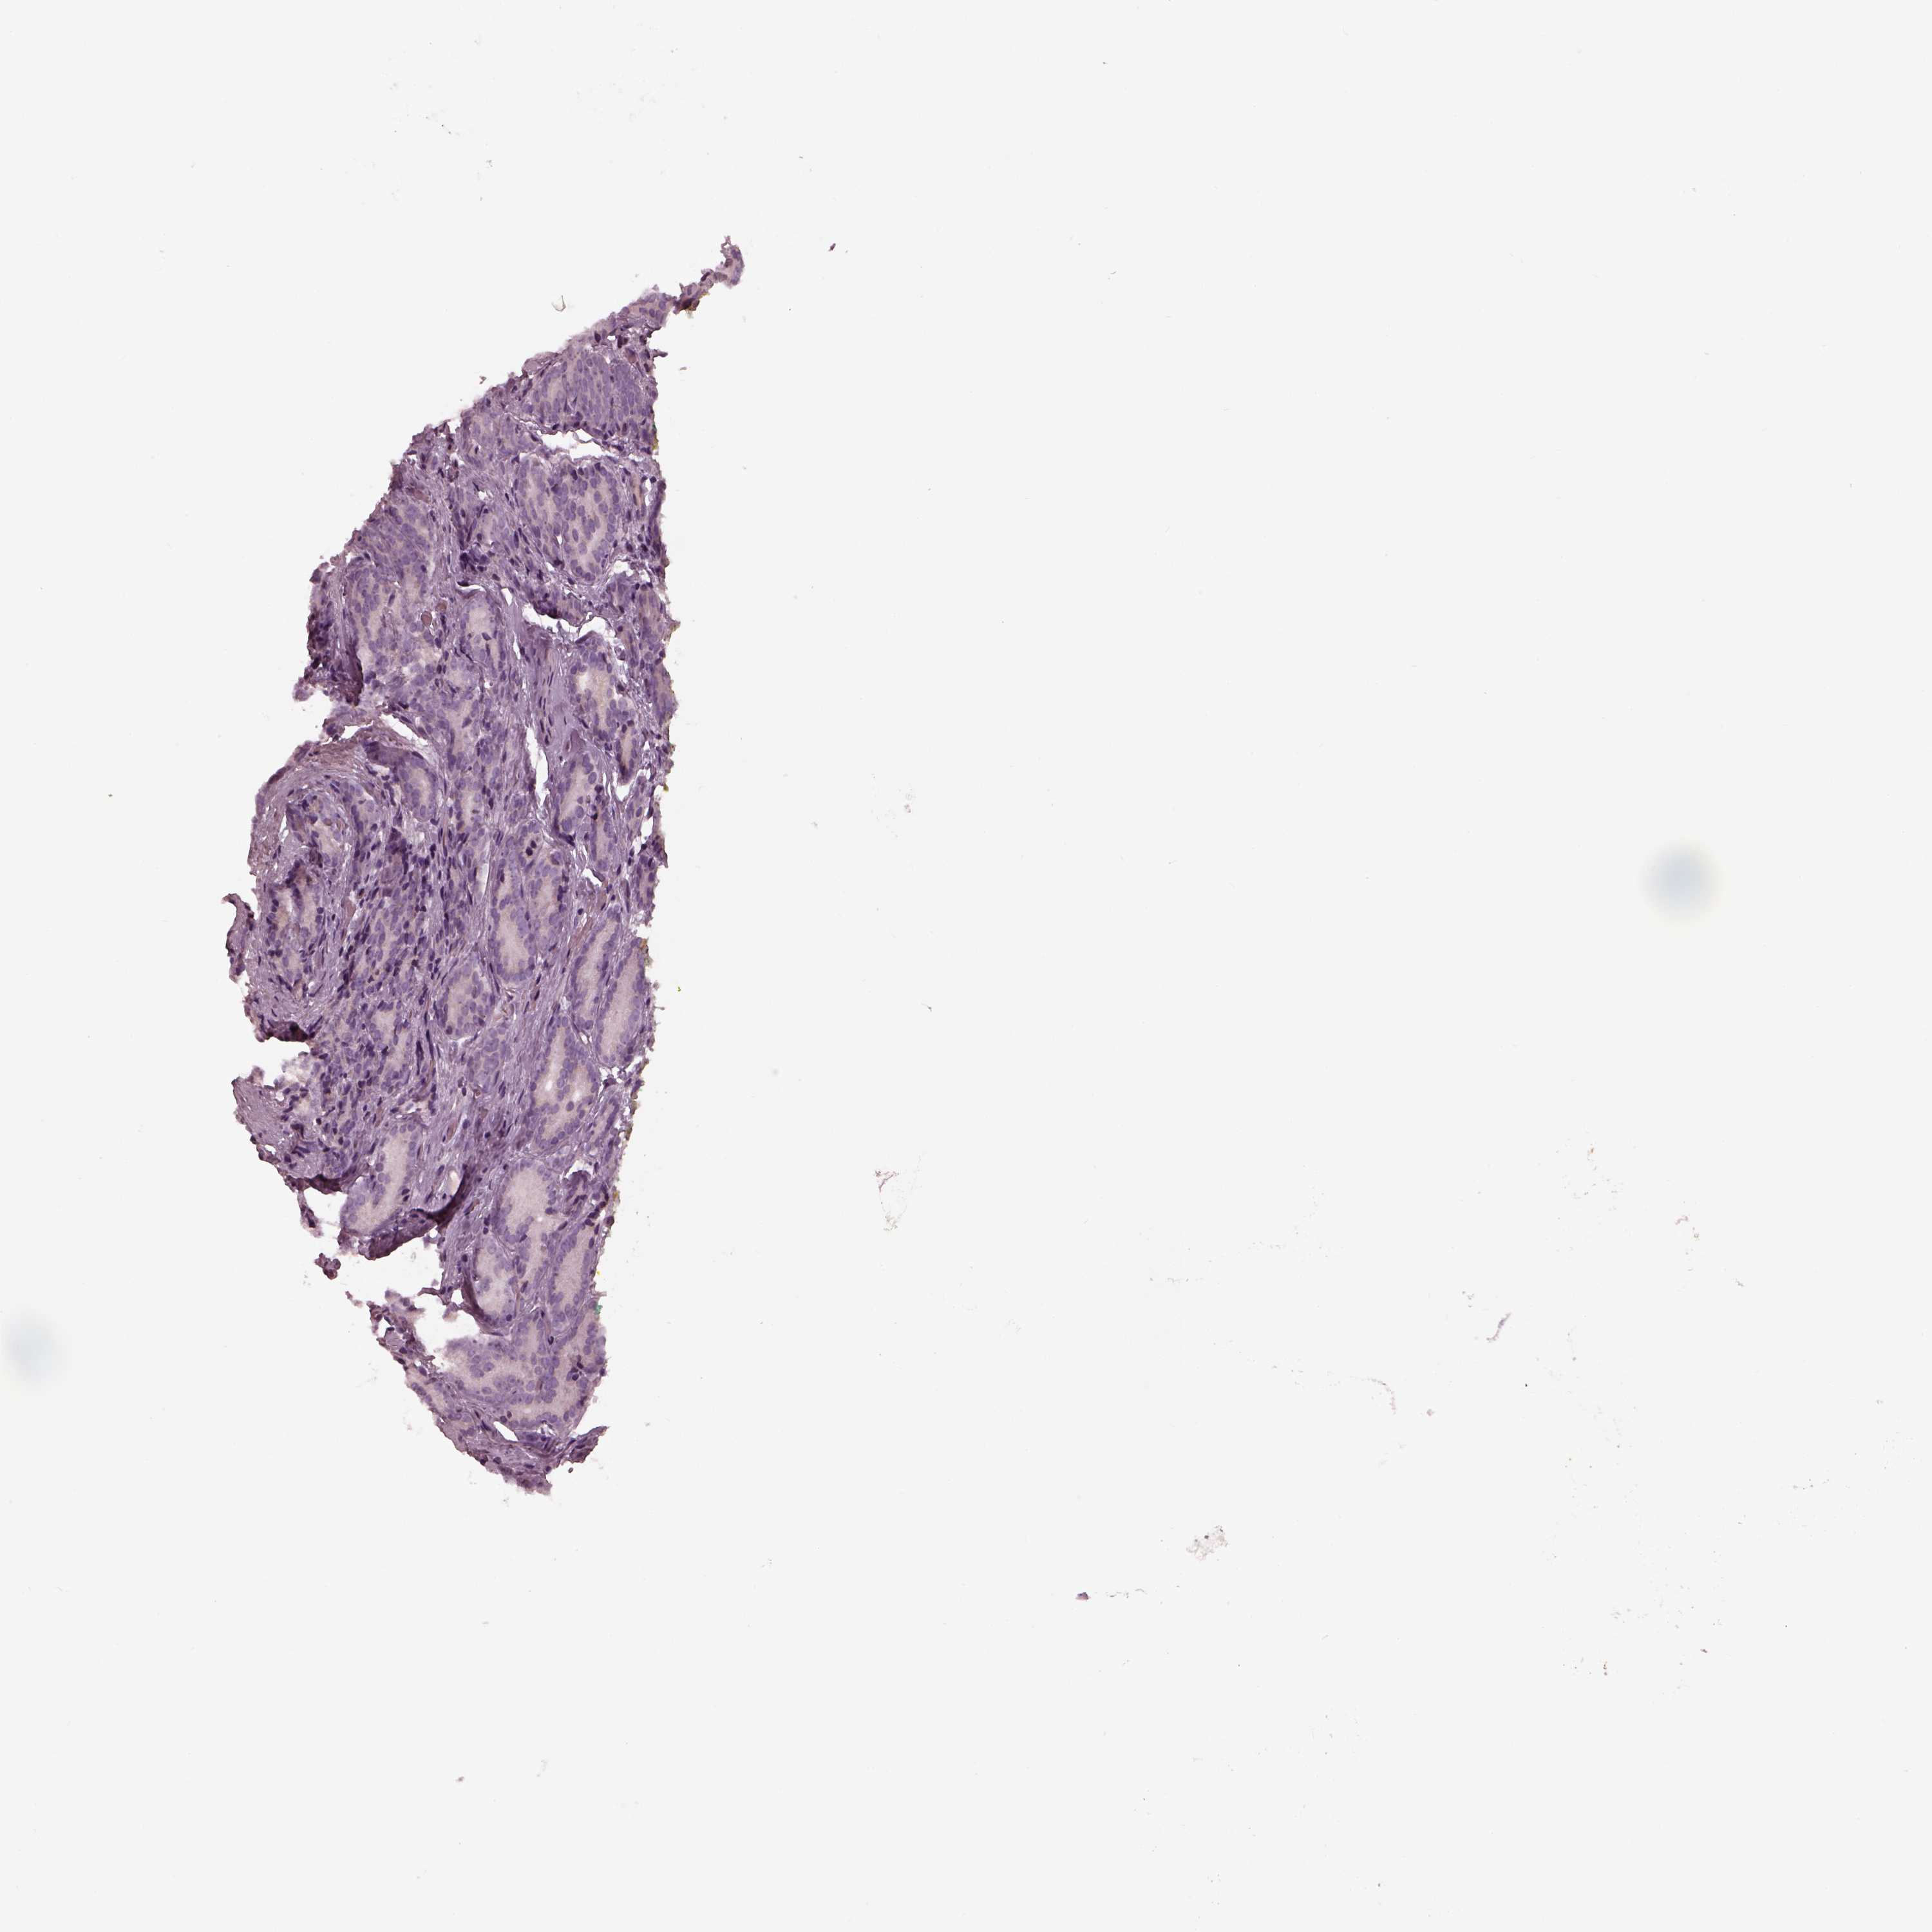

PROSTATE CANCER - Protein expressioni

A mouse-over function shows sample information and annotation data. Click on an image to view it in a full screen mode. Samples can be filtered based on level of antibody staining by selecting one or several of the following categories: high, medium, low and not detected. The assay and annotation is described here.

Antibody stainingi

Antibody staining in the annotated cell types in the current human tissue is reported as not detected, low, medium, or high, based on conventional immunohistochemistry profiling in selected tissues. This score is based on the combination of the staining intensity and fraction of stained cells.

Each image is clickable and will lead to virtual microscopy that enables deeper exploration of all samples and also displays staining intensity scores, fraction scores and subcellular localization as well as patient and tissue information for each sample.

Antibody HPA042369

Adenocarcinoma, NOS

Adenocarcinoma, High grade

Adenocarcinoma, Low grade